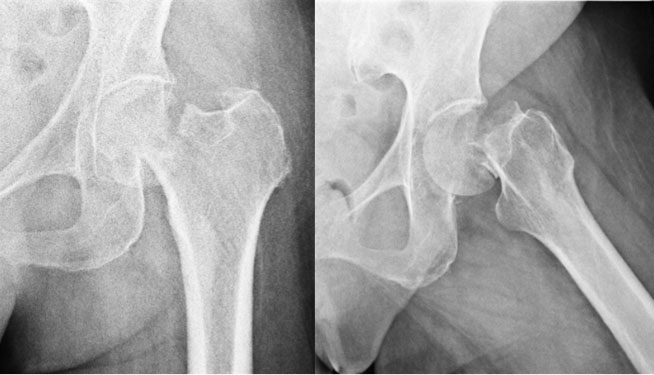

Getting up and active following surgery is vital to speeding up your recovery after a hip replacement. postop_lat

postop_lat from www.anteriorhipreview.com